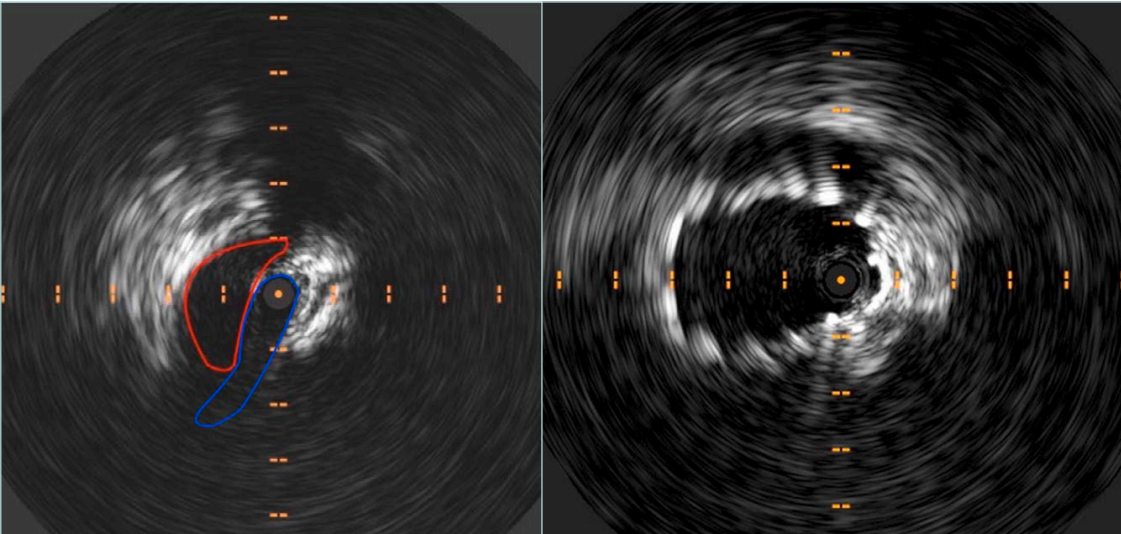

During interventions, IVUS allows precise assessment of the compressive lesion, measurement of luminal diameters, and identification of healthy vein segments both proximal and distal to the lesion—critical for determining optimal stent length and placement. This helps avoid common complications such as undersizing, which may result in stent migration or restenosis, and oversizing, which can lead to excessive radial force, vessel wall damage, and uncontrollable back pain. After stent deployment, IVUS is used again to verify that the stent is fully expanded, well-apposed to the vein wall, and that no residual stenosis or mechanical obstruction remains. Its integration into standard practice has been shown to significantly improve patency rates and reduce the risk of reintervention.14-16 (Figure 2).

Figure 2. Intravascular ultrasound (IVUS) showing preoperative compression at May-Thurner’s point and subsequent restored patency post stenting.